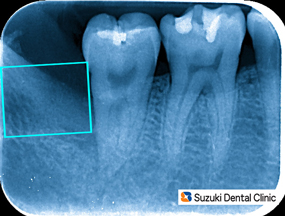

抜歯後の痛み

コラム「抜歯後の痛み」の画像